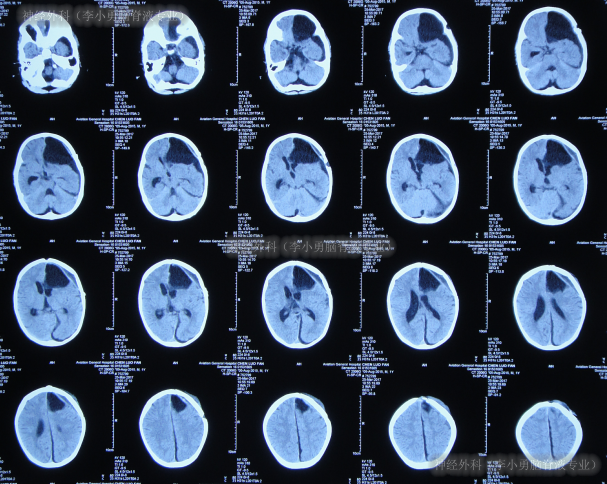

第2次手术软性神经内镜脑室内检查术和脑内囊肿造瘘术后10天即2017年5月14日,进行了第3次手术:脑室腹壁外引流术;术后当天查头颅CT后认为脑室有缩小(图-10)。

图-10:2017年5月14日头颅CT

第3次手术脑室腹壁外引流术19天即2017年6月2日,查头颅CT较2017年5月14日示未见脑室缩小(图-11)。

图-11:2017年6月2日头颅CT

第3次手术脑室腹壁外引流术37天即2017年6月20日,查头颅CT(图-12)后计划明天进行脑室腹腔分流术。

图-12:2017年6月20日头颅CT

第4次手术脑室腹腔分流术后3天即2017年6月23日,查头颅CT示脑室仍扩张(图-13)。

图-13:2017年6月23日头颅CT

第4次手术脑室腹腔分流术后20天即2017年7月10日,查头颅CT示脑室再次扩张更大(图-14)。

图-14:2017年7月10日头颅CT

第2次因脑积水在该院住院治疗83天内,先后进行了5次失败手术(硬膜下积液引流术、软性神经内镜脑室内检查术和脑内囊肿造瘘术后、脑室腹壁外引流术、脑室腹腔分流术、脑室腹腔分流管脑室端探查术)后仍脑积水,家属要求转至李小勇脑脊液专业。